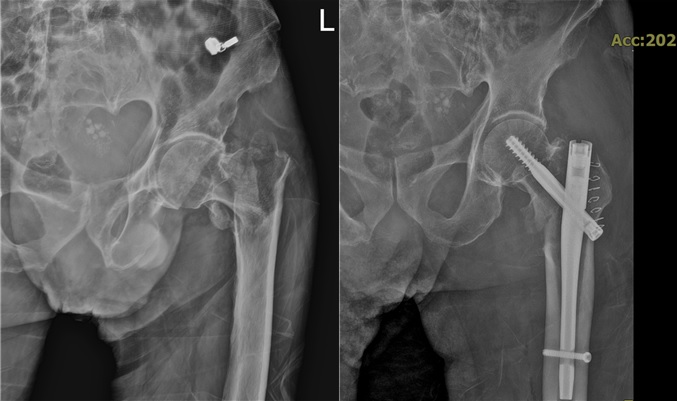

<»çÁøÀº ¼ö¼ú Àü°ú ÈÄ>

ÀμºÀÇ·áÀç´Ü ÇѸ²º´¿øÀÌ 100¼¼ Ãʰí·ÉÀÇ °íÀ§Çè ȯÀÚ¿¡°Ô ¹ß»ýÇÑ ´ëÅð°ñ °ñÀý ¼ö¼úÀ» ¼º°øÀûÀ¸·Î ¸¶Ä¡°í ȯÀÚ°¡ ¾ÈÁ¤ÀûÀΠȸº¹ ´Ü°è¿¡ µé¾î¼¹´Ù°í 16ÀÏ ¹àÇû´Ù.

À̹ø °í³µµ ¼ö¼úÀº ÇѸ²º´¿ø Á¤Çü¿Ü°ú ±èÀº¿ °úÀåÀ» Áß½ÉÀ¸·Î ôÃß·°üÀý¼¾ÅÍ, ½ÉÀå³»°ú, ÈäºÎ¿Ü°ú, ÁßȯÀÚ½Ç µî ¿©·¯ Àü¹® ÀÇ·áÁøÀÌ ±ä¹ÐÇÏ°Ô Çù·ÂÇÏ´Â ´ÙÇÐÁ¦ ½Ã½ºÅÛÀ¸·Î ÁøÇàµÆ´Ù.